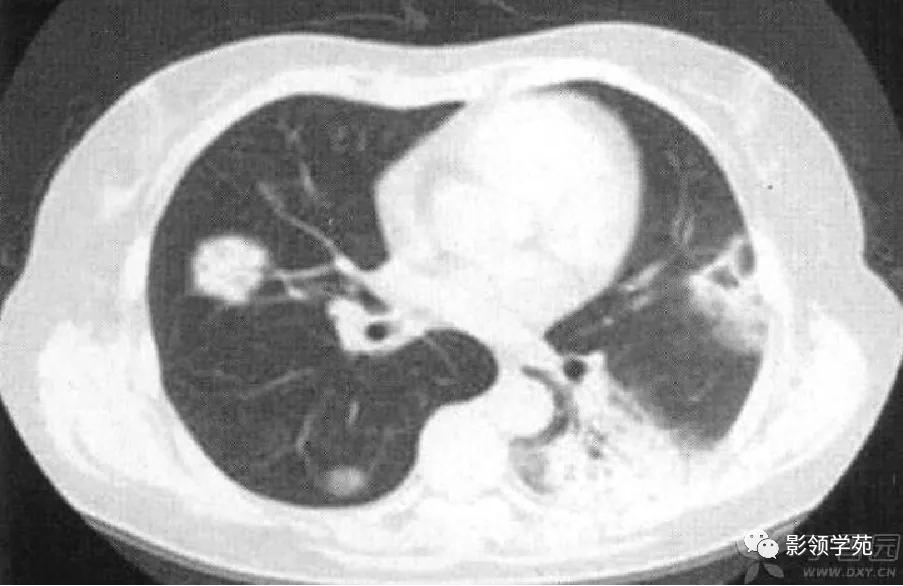

肺实变多由于肺泡出血所致,毛玻璃样密度影代表肺实变的早期阶段。楔形病灶是另一类较常见肺部CT 表现,肺梗死的病理基础是坏死性血管炎累及小动脉及小静脉引起的出血性肺梗死,CT表现为肺内楔形病灶,边缘清楚或不清楚,尖端指向肺门,宽基底位于胸膜面,可以看到血管进入征象及胸膜的增厚。

病例5:左下叶肺梗死,左肺下叶楔形病灶,边缘清楚,宽基底位于胸膜面,尖端指向肺门。

病例8:右上肺胸膜下病灶,伴厚壁空洞,邻近胸膜楔形增厚。